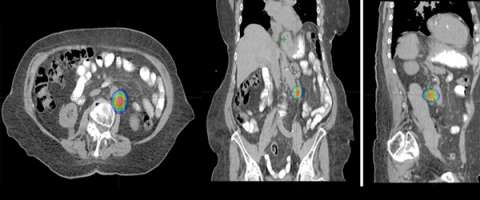

Similarly, because this specialized form of radiation involves the use of multiple radiation beam angles, expert Radiation Oncologists specialized in this technique are able to safely deliver high doses of radiation, with very sharp dose gradient outside the tumor and into the surrounding normal tissue (Figure 3).

The second row shows images (axial, coronal, and sagittal) of the distribution of the radiation dose that was delivered to this area. One can see that the dose of radiation to this target is very tightly distributed to avoid as much normal tissue as possible.